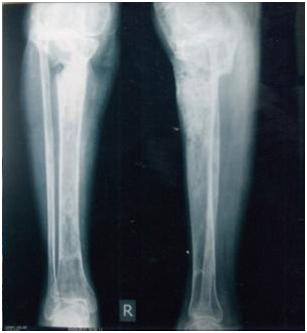

Figure 10 Clinical result and appearance of the patient after 6 months.